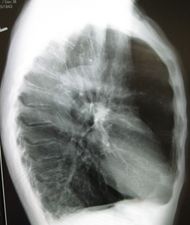

| A lateral chest x-ray of a person with emphysema. Note the barrel chest and flat diaphragm. | |